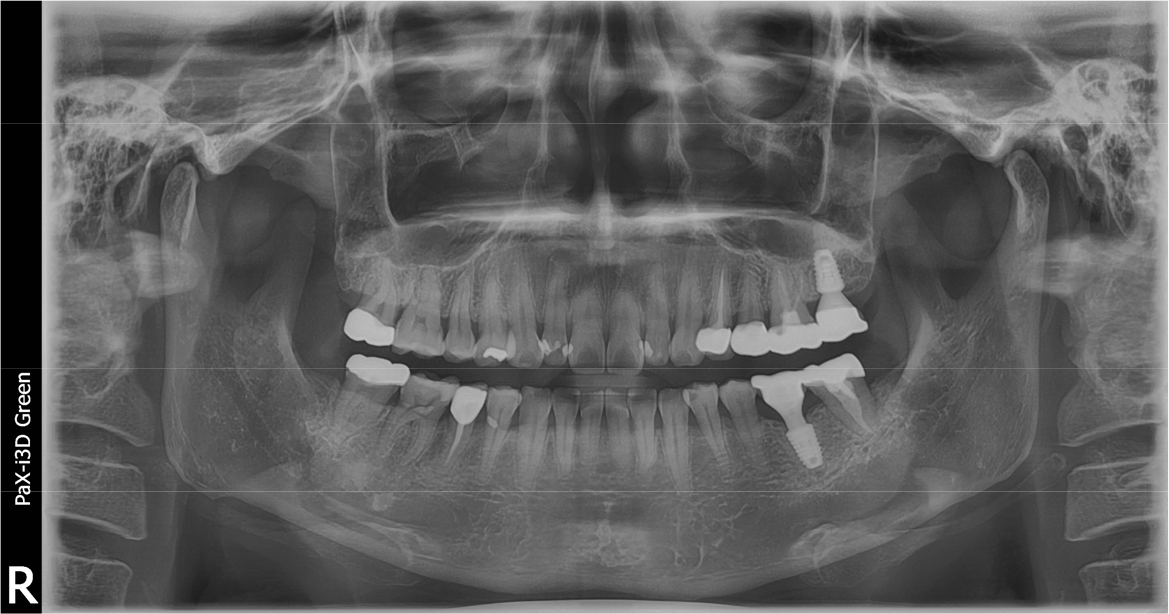

A 43-year-old female needing implant treatment and extraction of the upper left molar visited the clinic. Her upper left second molar showed second degree of tooth mobility and had a treated history of intentional replantation (Table 1). The apical lesion of this tooth disappeared after the intentional replantation (Fig. 1A, 1B). There are no signs of additional infection or periodontitis-related inflammation (Fig. 2). The alveolar bone height of this site was more than 5 mm, which facilitates the treatment plan to conduct the immediate implant placement with elevation of the maxillary sinus membrane using hydraulic pressure.

After 4 months of the first surgery, the ISQ value was 71, showing favorable stability, the prosthesis was placed consecutively, and healing progress was observed (Fig. 8A, 8B). After 5 months, the final prosthesis was completed (Fig. 9A, 9B). Supported treatment was initiated and radiographs were taken after 6 months (Figs. 10, 11, 12). In the radiograph analysis, the alveolar bone surrounding the dental implant was stable, with ossified bone verified. In a 6-month interval, the supported treatment was conducted in April 2022, showing no signs of peri-implant gingivitis or bone resorption (Figs. 13 and 14).